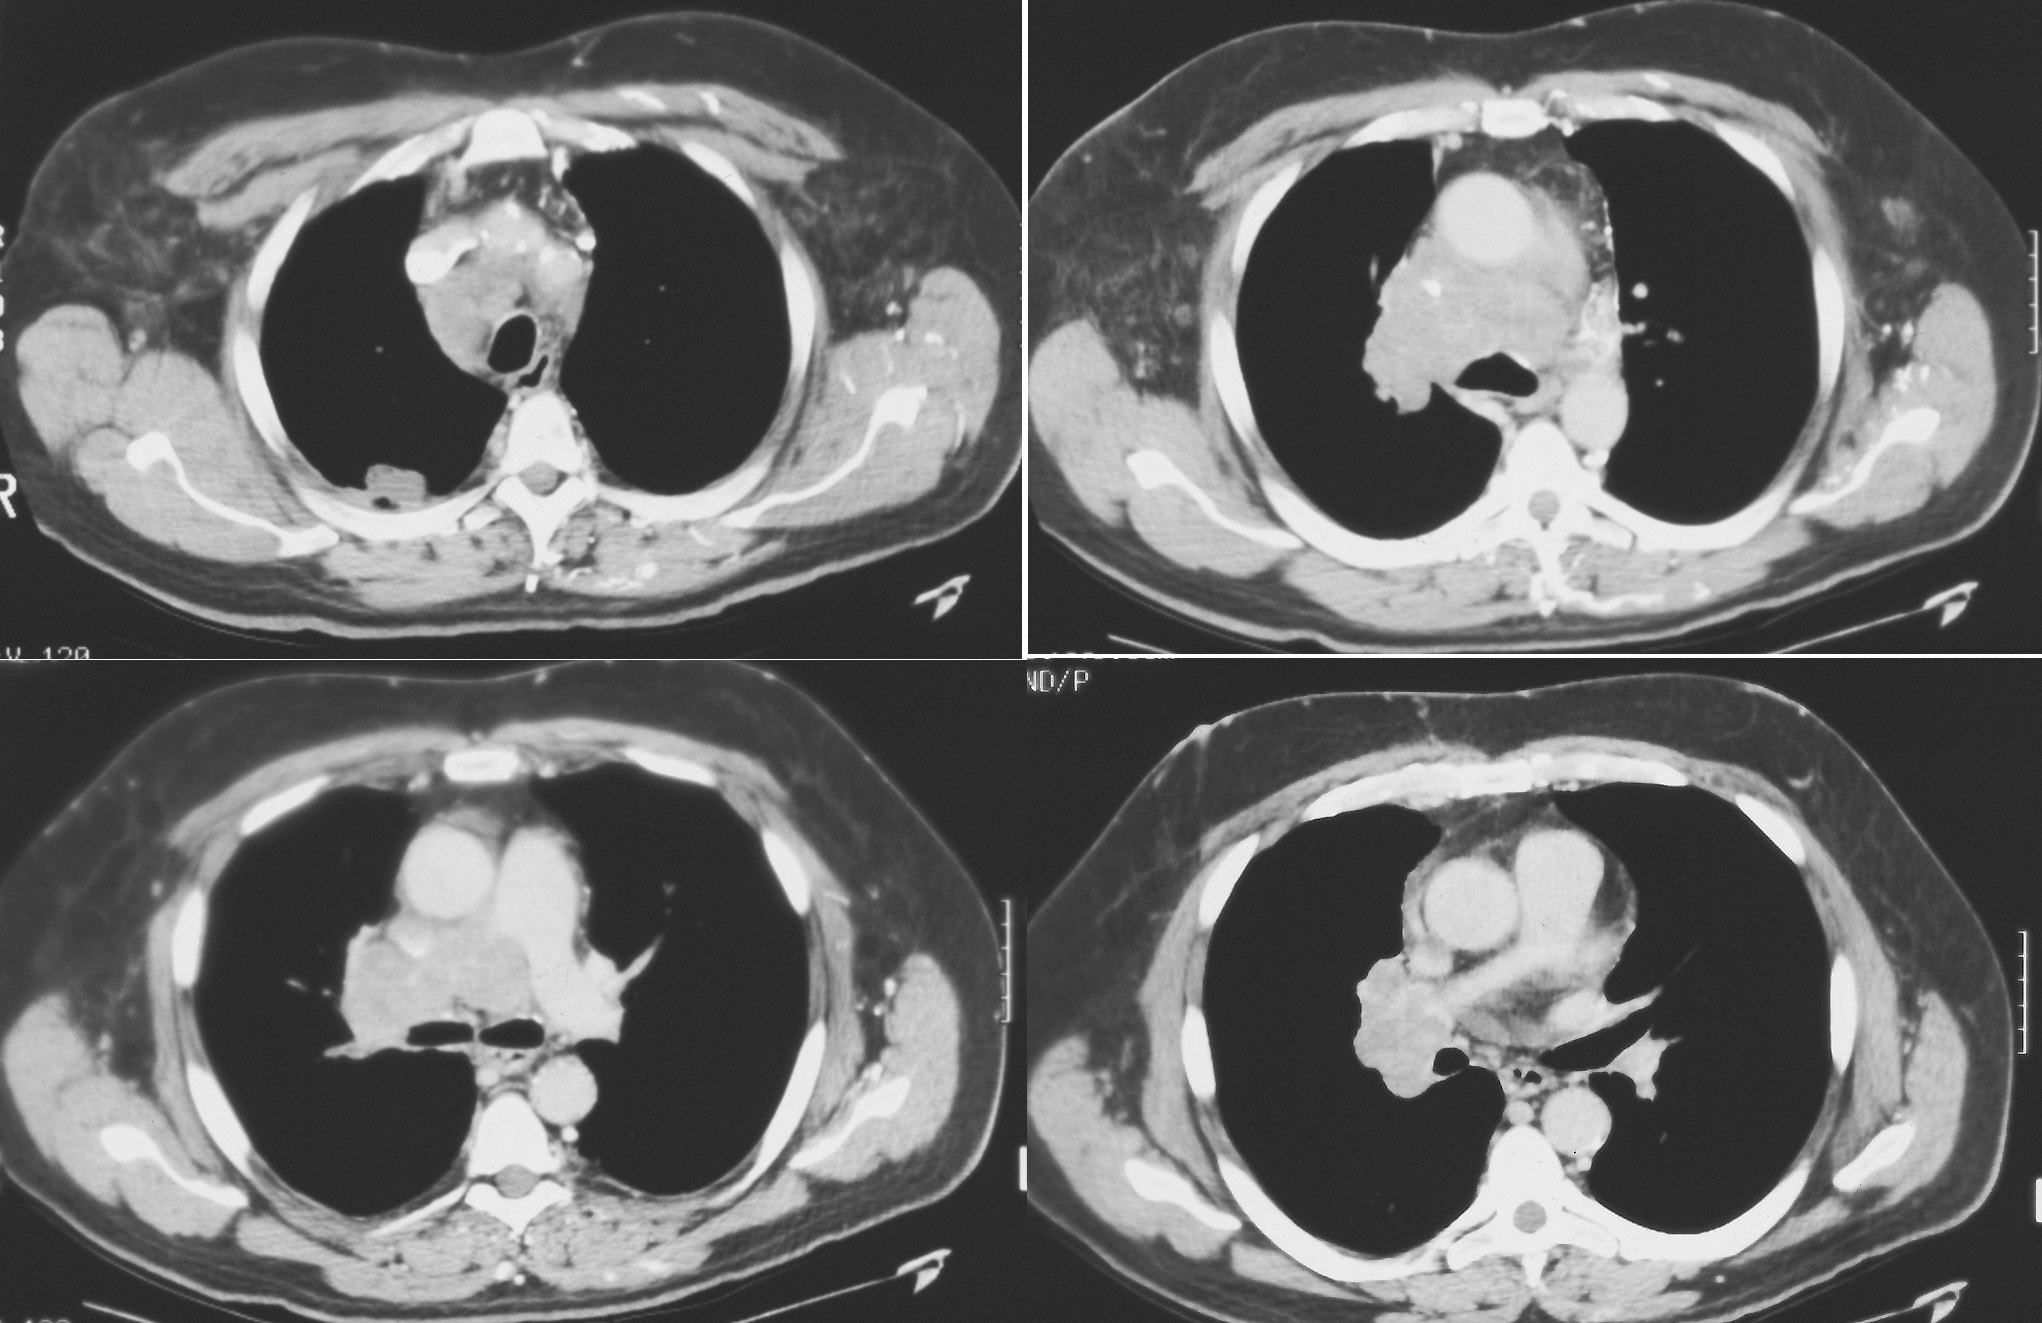

◂Chest CT for Internal Medicine Residents